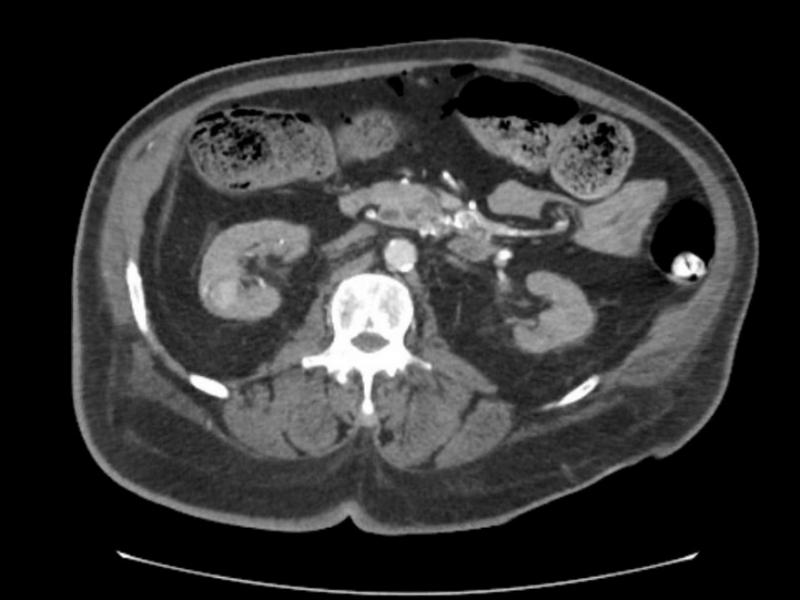

A 65 yo male with a history of ESRD/HD, DM, HTN, CAD, PAD